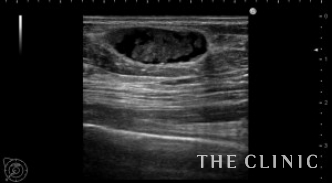

エコーでは、右胸に2㎝大の充実成分を含む腫瘤を認めました。他にも小さなオイルシストが散在していました。

右の充実性のしこりです。